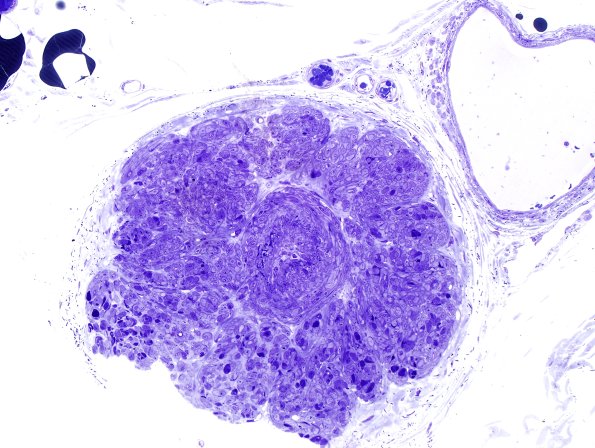

I think this represents a vascular malformation composed largely of smooth muscle cells with disruption of the internal elastic lamina. Other thoughts are welcome. (plastic sections)